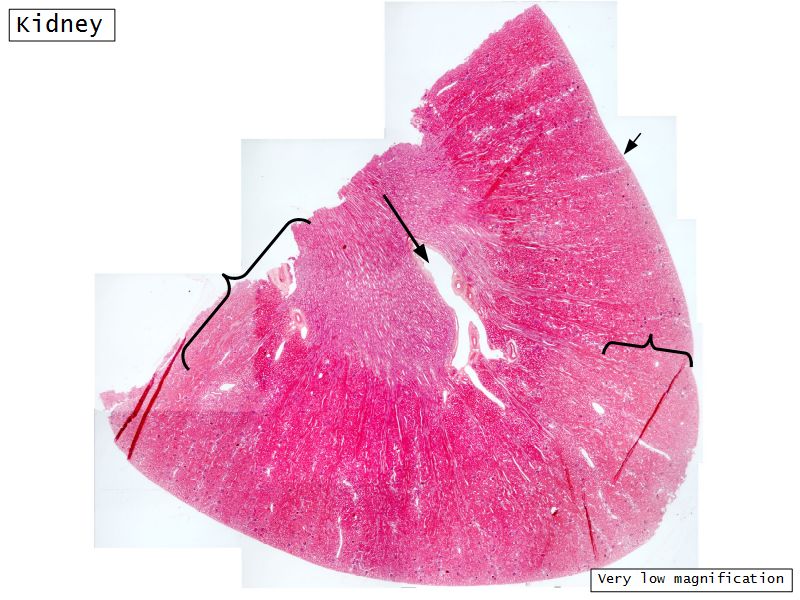

Kidney

- Capsule

- Cortex

- Medulla

- Multilobar

- Make an annotated drawing of the macroscopic view of the kidney.